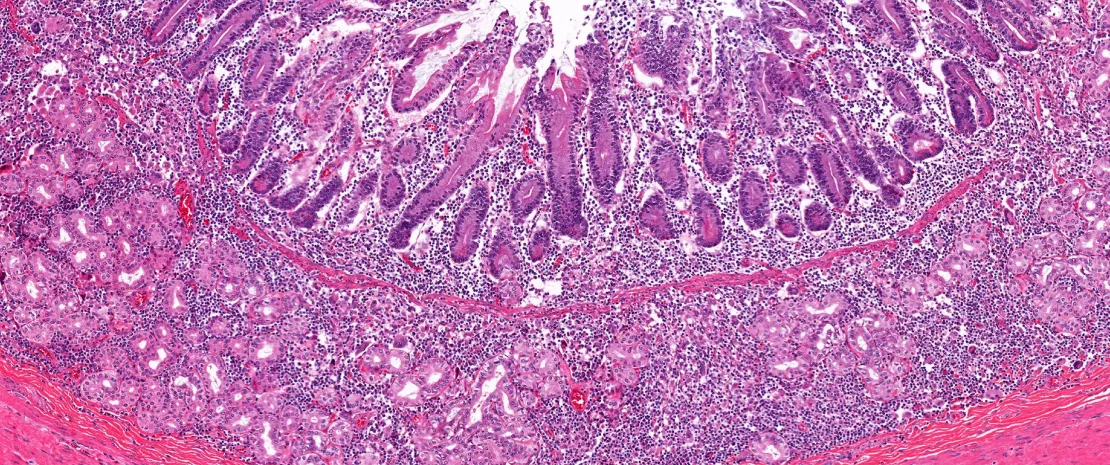

En testant 89 souches microbiennes, les chercheurs ont constaté que la capacité de bioaccumulation des PFAS varie considérablement d’une bactérie à l’autre : 38 souches, dont les bactéries du phylum des Bacteroidota, se montrent particulièrement bio-accumulatrices. Et ce, même à des concentrations faibles de PFAS. Le processus se révèle très rapide (quelques minutes suffisent), définitif (pas de relargage) et très efficace : la concentration intracellulaire en PFAS des bactéries est de l’ordre de 50 fois supérieure à celle du milieu, atteignant le millimolaire. Plus la molécule de PFAS est longue, plus elle est bioaccumulée par la bactérie.